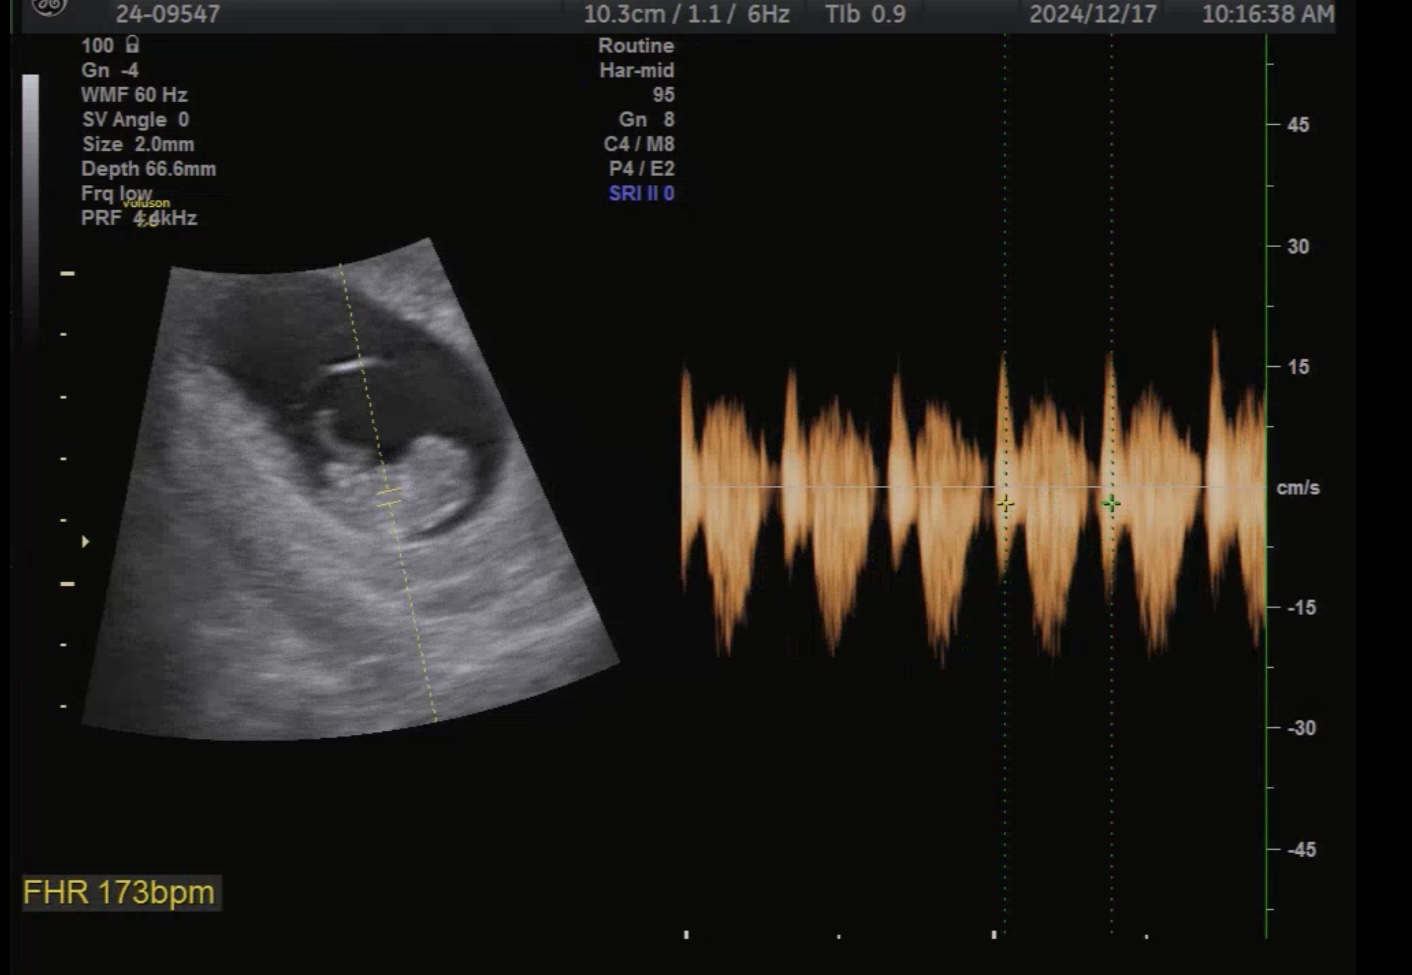

산부인과 정기진료 초음파

9주 2일차,

초음파 상 태아의 심장 박동수는

173bpm으로 규칙적으로 뛰고 있었고,

현재까지 별다른 이상 소견은 없었다.